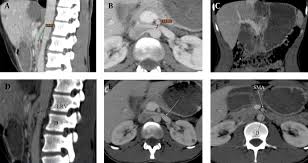

Smas superior mesenteric artery syndrome. Whatever the name this rare condition arises when the duodenum becomes compressed between the aorta and superior mesenteric artery. This compression causes partial or complete blockage of the duodenum. Superior mesenteric artery syndrome SMAS is an unusual condition where the third part of the duodenum is compressed between the superior mesenteric artery and the aorta.

This compression causes partial or complete blockage of the duodenum. Superior mesenteric artery syndrome SMAS is a rare gastrointestinal disorder characterised by vascular compression of the third part of the duodenum in the angle between the superior mesenteric artery SMA and the abdominal aorta. SMA Syndrome may also be known by several other names including SMAS Wilkie Syndrome Cast Syndrome arteriomesenteric duodenal obstruction and chronic duodenal ileus.

Superior Mesenteric Artery Syndrome SMAS Superior mesenteric artery syndrome SMAS is a digestive condition that occurs when the duodenum the first part of the small intestine is compressed between two arteries the aorta and the superior mesenteric artery. Superior mesenteric artery syndrome SMAS is a digestive condition that occurs when the duodenum the first part of the small intestine is compressed between two arteries the aorta and the superior mesenteric artery. Superior mesenteric artery SMA syndrome is a gastro - vascular disorder in which the third and final portion of the duodenum is compressed between the abdominal aorta AA and the overlying superior mesenteric artery.

Axial Ct Section Demonstrating The Anatomy Of Sma Syndrome Download Scientific Diagram